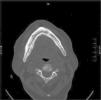

Fístulas mandibulares en una mujer de 75 años